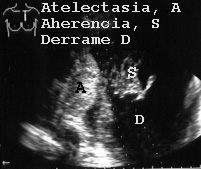

En la Fig 53 se observa un derrame con adherencias y una atelectasia.